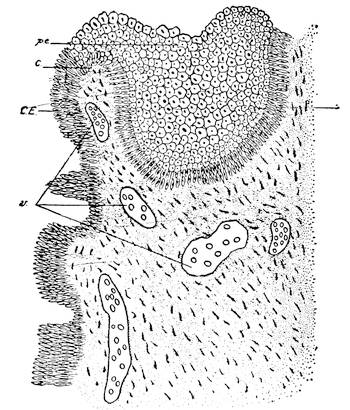

Mons of Venus, labia majora, minora, vestibule, bulbs, clitoris, Bartholinian glands, hymen, vagina, uterus, broad and round ligaments, viiitubes, ovaries, Graafian follicle, ovum.

Before the Wolffian body has yet degenerated the mesothelial cells overlying the free surface of that body, at its upper part, and at the ventro-mesial side, assume a high columnar form and form an elongated swelling, known as the internal genital ridge. As the degeneration of the Wolffian body proceeds the genital ridge is differentiated into the indifferent sexual gland, by producing a projection upon the wall of the coelom or body cavity. This prominence is attached to the surface of the Wolffian body by a fold of the peritoneum. At this stage there is no distinction of sex. The sexual gland represents the indifferent type of the sexual apparatus.

The ovary is produced from the asexual stage by the following metamorphosis. The mesothelial cells on the peritoneal surface of the sexual gland change into the germinal epithelium and form the so-called egg-columns or sexual cord which represent the primitive ova.